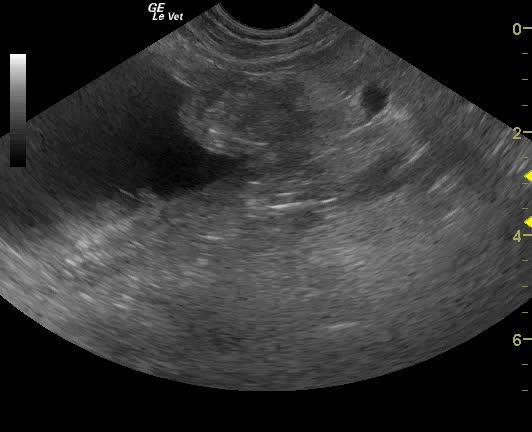

A 9-year-old intact female Brittany Spaniel dog, with previous history of cystotomy, was presented on emergency at a 24-hour facility for vomiting, shaking, painful abdomen, and extreme lethargy. Physical examination found the patient whining and crying, depressed, with tacky mucous membranes, and a firm distended abdomen. The patient was ambulatory but was most comfortable in sternal recumbency. Abnormalities on CBC and blood chemistry included leukocytosis, increased BUN, and mild hypoalbuminemia. Coagulation panel was within normal range.

A 9-year-old intact female Brittany Spaniel dog, with previous history of cystotomy, was presented on emergency at a 24-hour facility for vomiting, shaking, painful abdomen, and extreme lethargy. Physical examination found the patient whining and crying, depressed, with tacky mucous membranes, and a firm distended abdomen. The patient was ambulatory but was most comfortable in sternal recumbency. Abnormalities on CBC and blood chemistry included leukocytosis, increased BUN, and mild hypoalbuminemia. Coagulation panel was within normal range. Survey radiographs showed generalized loss of detail (consistent with free fluid) and a linear radiodensity in the cranial abdomen. Despite being a poor surgical candidate, the patient was recommended for immediate exploratory surgery due to concern of a ruptured pyometra.